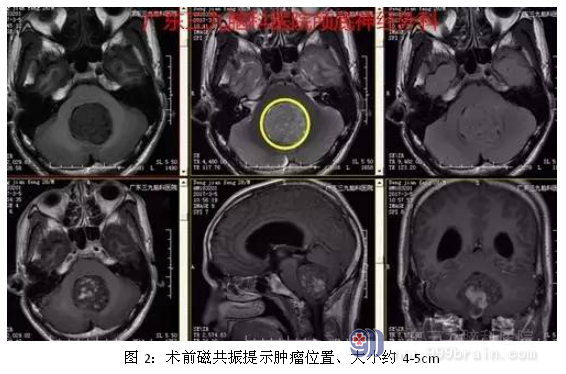

入院后完善术前相关检查,术前磁共振提示肿瘤大小约4-5cm,术前CTA提示肿瘤血供丰富,行全麻下小脑蚓部占位性病变切除术,术中肿瘤全切,术后恢复良好。术后诊断:小脑蚓部髓母细胞瘤。

此瘤诊断要点:发病部位及由此而引起的间接征象。典型髓母细胞瘤位于第四脑室顶部及小脑蚓部,边界清楚,大小约4-5cm之间,可向各个方向生长而进入四脑室或周围脑池,易经脑脊液在脑室和蛛网膜下腔内转移。引起的临床症状为头痛、头晕、恶心、呕吐,双眼球震颤,视物不清,颈部抵抗感,步态不稳及共济失调等小脑症状。本病人因发作性头晕头痛恶心呕吐就诊,症状较重,符合临床特点。